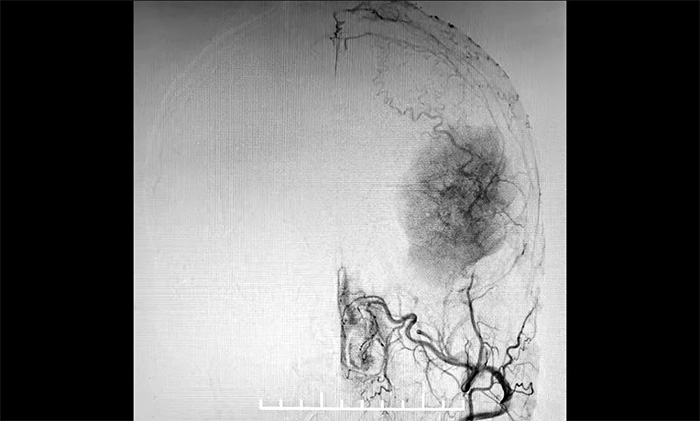

發生於額顳部位的巨大腦膜瘤,治療方法主要為顯微外科手術切除。該腫瘤不僅體積巨大,橫跨多個重要腦功能區,行DSA檢查發現,腫瘤包裹纏繞多根重要的動脈血管,血供十分豐富。若直接行手術切除腫瘤,容易因術中大出血而危及患者生命。

▲ DSA檢查示:腫瘤血供豐富